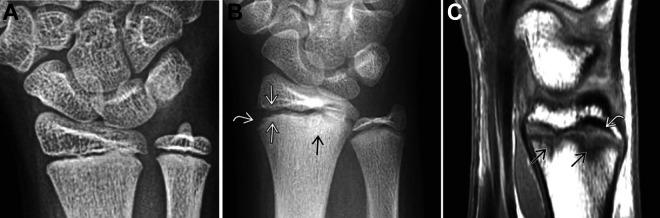

Wrist injuries in the competitive athlete are a common reason for evaluation related to an acute injury or after symptoms have become chronic. While radius- and ulna-sided wrist pain are common topics covered in the literature, middorsal wrist pain is more common than the available literature would suggest. Missed diagnoses and inadequate treatment can significantly increase athlete morbidity and delay return to play. The goal of this article was to review the differential diagnosis of middorsal wrist pain in the athlete and discuss the diagnosis, treatment, and early return to play for each condition.

竞技运动员的腕部损伤是因急性损伤或症状转为慢性后进行评估的常见原因。虽然文献中常见的话题是桡侧和尺侧腕部疼痛,但腕背中部疼痛比现有文献所显示的更为常见。漏诊和治疗不当会显著增加运动员的发病率并延迟重返赛场的时间。本文的目的是回顾运动员腕背中部疼痛的鉴别诊断,并讨论每种情况的诊断、治疗及早期重返赛场的问题。